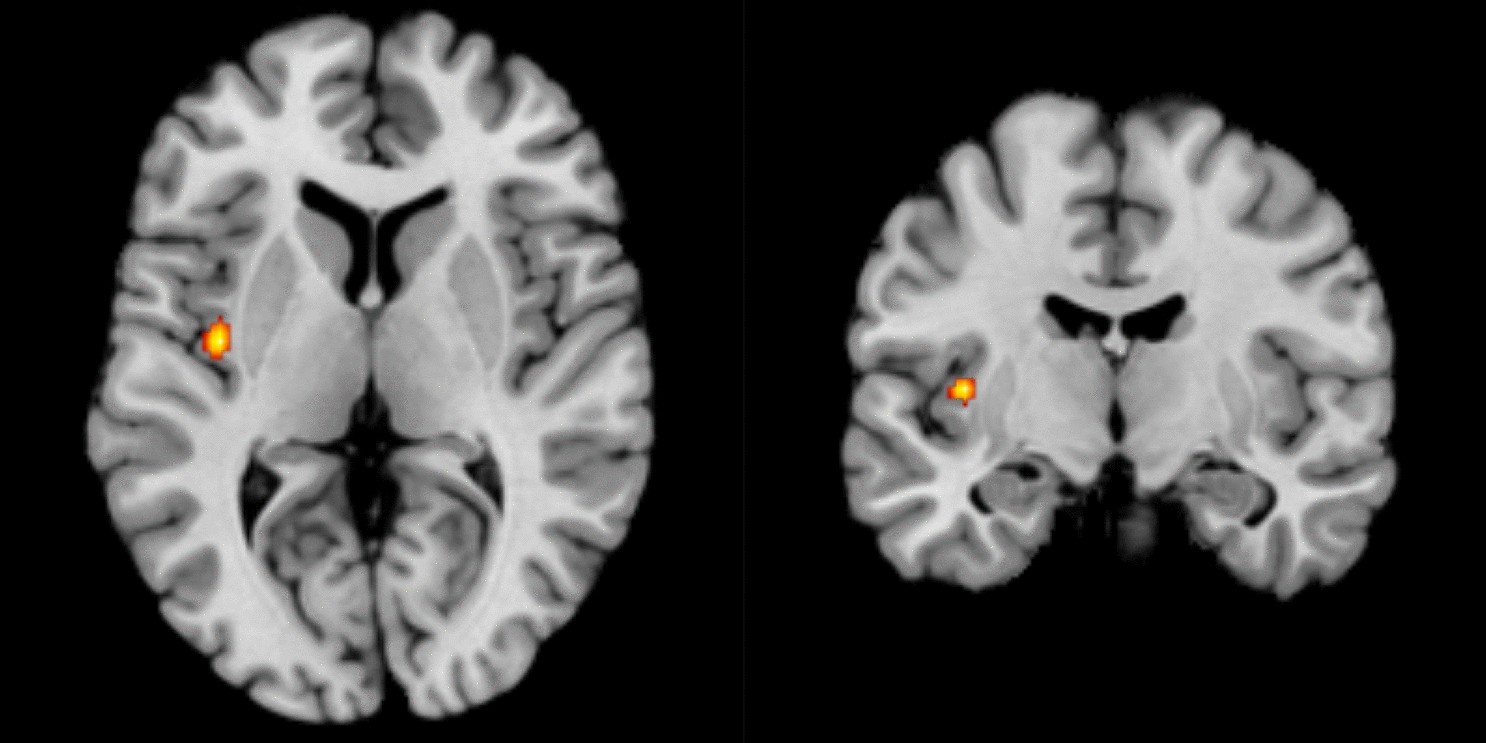

Insula Activity In Resting State Differentiates Bipolar From Unipolar Depression A Systematic Review And Meta Analysis Scientific Reports